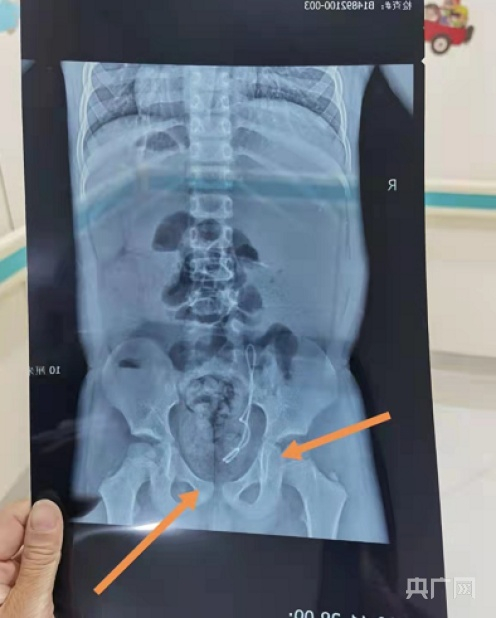

复查时,院方称二次放管的位置偏低,需要重新进行全麻手术,再进行放管。(央广网发 患者家属供图)

“第二次手术复查后,王某晖告诉我们,孩子这次手术放管的位置偏低,需要重新进行全麻手术,再进行放管。要不然就是把管取出来,进行造瘘。这不得不让我们对省医的手术治疗和补救方案产生质疑。”焦女士称。

焦女士产生质疑:患者在第一次手术观察中已出现血尿,且第二次手术,双J管未放到肾盂处,而是放在膀胱内,省医的主治大夫为何坚持称属正常情况?她认为,省医的治疗方案有问题。此外,患者家属表示不清楚第二次放管是谁在手术,“为何大夫每次手术结束均称放管很顺利、很成功,让家属放心,却是接连失败?”